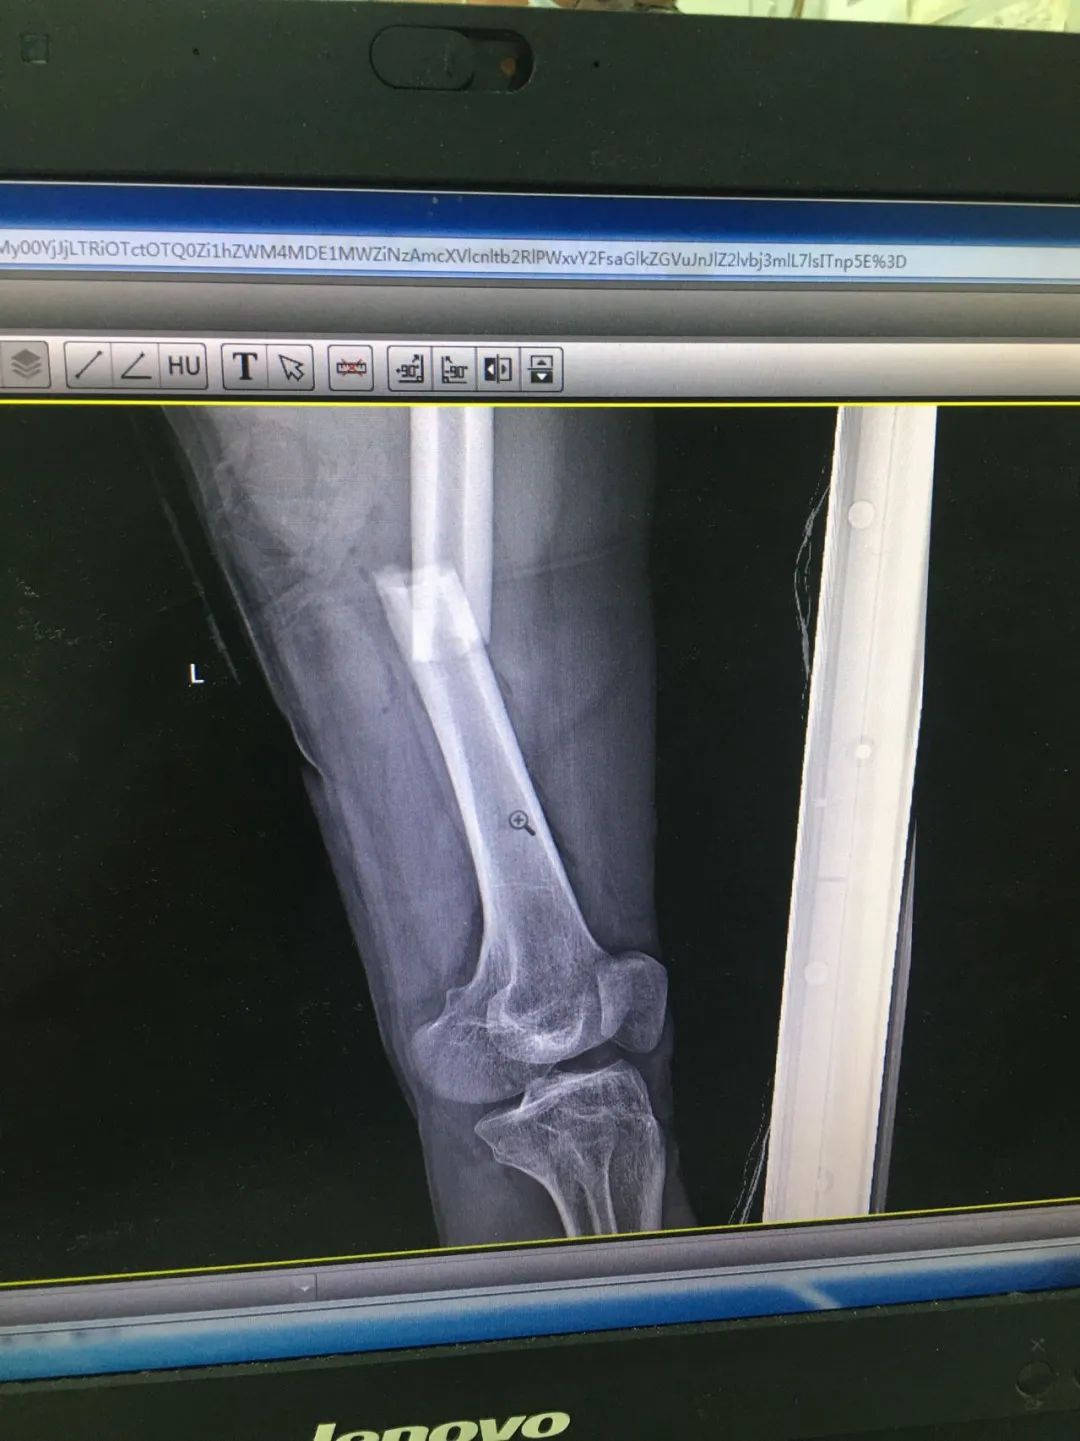

入院時(shí),劉先生已失血性休克。急診科為劉先生安排X線及CT攝片檢查,顯示左股骨干、左腓骨上端骨折,左脛骨遠(yuǎn)端粉碎性骨折,頭皮及全身多處皮膚軟組織挫裂傷,隨后收治于骨科。

第1次手術(shù)10天后,骨科為劉先生安排了第2次手術(shù),歷經(jīng)3個(gè)小時(shí),成功完成左股骨干骨折及左脛骨遠(yuǎn)端骨折閉合復(fù)位內(nèi)固定術(shù),植入兩根30cm×10mm、34cm×10mm髓內(nèi)釘。

術(shù)后一周,患者手術(shù)切口愈合良好,左下肢皮膚感覺(jué)及肌力正常,左足末梢循環(huán)恢復(fù),復(fù)查X片顯示骨折復(fù)位標(biāo)準(zhǔn),內(nèi)固定物位置良好。